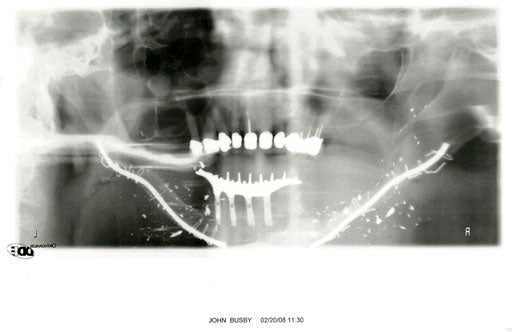

Dr. David Keith/Mass. General

An X-ray of John Busby's lower face. His jawbones were shattered, most of his teeth were gone, his tongue was almost severed and his chin was hanging down onto his chest. He had to undergo 18 years of reconstructive surgery. Had the bullets passed an inch higher or farther back, Busby would have bled to death or died from brain damage.